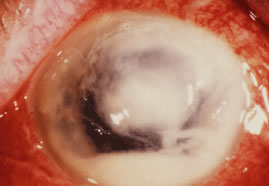

In the early stages of infection, filamentous fungi produce signs that are readily distinguishable from yeast or bacterial keratitis. The most distinctive sign is the presence of delicate, fine, feathery, opalescent, gray-white or yellow-white material in the anterior stroma, surrounded by scant cellular infiltrate or edema (Fig. 1). The epithelium may be intact. The overlying epithelium may be granular and the surface elevated and irregular in contour. Linear infiltrates typically extend into the adjacent stroma. Multiple discrete opacities may develop outside the perimeter of the principal focus of inflammation, either separated by clear stroma or linked by fine linear collections of inflammatory cells and material (Figs. 2 and 3). In the absence of inflammation in the adjacent stroma, branching hyphal fragments may be visualized by biomicroscopy (Figs. 4 and 5). Confocal microscopy may also detect hyphal elements within the stroma.28,29 Peripheral infection resembles noninfectious marginal infiltrative and ulcerative keratitis (Fig. 6). Multifocal keratitis may develop after contact lens wear or injury by multiple projectiles (Fig. 7). In the early stages, iritis is present and the intraocular pressure remains normal. Inappropriate, empirical therapy of fungal keratitis with topical fluoroquinolone or aminoglycoside antibiotics may suppress or eliminate the superficial elements but allow extension of the organisms into the stroma because these agents may possess selective antifungal activity.4,30,31

There is no distinguishing clinical sign by which to recognize the genus or species of the infectious filamentous fungus. F. solani is the most virulent organism and typically produces rapidly progressive infection characterized by epithelial and stromal ulceration, dense stromal necrosis, abundant cellular infiltrate, and edema in the adjacent stroma and hypopyon (Figs. 8 and 9). Delicate feathery components are transient. Individual hyphal fragments are rarely visualized. Infection by certain species of Aspergillus and Scedosporium (Figs. 10 and 11) resembles F. solani keratitis and progresses rapidly. Infection by less virulent organisms, such as Curvularia and Alternaria species, produces small, focal (less than 3-mm diameter) areas of nonnecrotizing stromal inflammation with delicate feathery borders (see Fig. 1 and Fig. 12). Macroscopic pigmentation may develop in keratitis caused by Alternaria, Curvularia, and other dematiaceous fungi (Fig. 13).4,11,14 The central component may progress to dense, opaque, gray-white suppuration in the deep stroma without enlargement in total area and may be accompanied by mild inflammation in the adjacent stroma. Iritis is minimal to moderate. Infection caused by other, relatively less virulent organisms resembles herpes simplex or noninfectious keratitis (Fig. 14).

Candida infection typically produces epithelial ulceration, focal necrotizing stromal inflammation, moderate cellular infiltrate and edema in the adjacent stroma, and mild or moderate iritis in the early stages, indistinguishable from bacterial keratitis (Figs. 15, 16, and 17). Fungal elements cannot be detected by biomicroscopy. If untreated, the keratitis evolves to produce dense suppuration and necrosis of the deep stroma. Although multifocal suppuration may develop in polymicrobial keratitis, there is no distinctive sign of mixed Candida and bacterial infection (Fig. 18).

Advanced, severe filamentous fungal or yeast keratitis is indistinguishable from keratitis caused by virulent bacteria such as Staphylococcus aureus or Pseudomonas aeruginosa. The area of epithelial and stromal ulceration is large. Dense, opaque, homogenous, yellow-white stromal necrosis develop and is surrounded by confluent cellular infiltrate and full-thickness stromal edema (Figs. 19, 20, 21). Hyphal elements may penetrate Descemet's membrane and endothelium and be visualized in the anterior chamber. Fibrinous material accumulates over the endothelium, anterior chamber angle, and iris. Pain is typically severe. Secondary ocular hypertension may ensue. Progressive stromal necrosis leads to corneal perforation and, rarely, consecutive endophthalmitis.